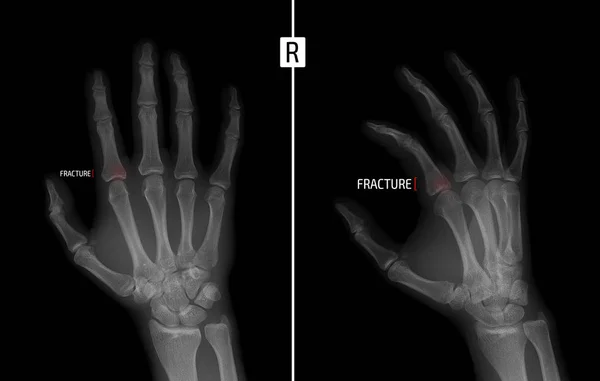

A seconda della causa, i traumatologi distinguono le fratture traumatiche e patologiche (come suggerisce il nome, il primo tipo è causato da un trauma, e il secondo da malattie specifiche, come l'artrite, l'osteomielite o l'osteoporosi). Da circa 26 giorni ho subito un operazione alla 1 falange del pollice della mano destra, mi hanno inserito 2 fili di kirschner e fin qua tutto ok. Le fratture alle falangi della mano e del piede sono molto comuni negli adulti e nei bambini.

La falange delle membra dell'uomo consiste di tre parti: Normalmente è più facile che ad essere colpite da una frattura siano le punta delle dita, in questo caso si parlerà di frattura dell'articolazione interfalangea distale. Salve circa trenta giorni fa mi sono fratturato la falange distale del v dito della mano destra con avulsione parcellare. L'articolo del dottor giuseppe checcuci. Possono interessare le ossa metacarpali del palmo della mano o le falangi delle dita. La falange delle membra dell'uomo consiste di tre parti: Il gruppo delle falangi rappresenta la porzione scheletrica distale di ciascuna mano e ciascun piede. Cosa devo fare perchè mi passi più in fretta!!!! La mano y la muñeca humanas están compuestas por tres grupos de los carpos son la base de la mano y la muñeca, y consisten en ocho huesos pequeños con diferentes nombres. Quando si verifica una frattura delle falangi della mano è necessario intervenire in un primo. Frattura delle dita della mano, sintomi, terapia. Le fratture della falange distale sono trattate in base alla sede della frattura e le indicazioni vanno da una riduzione aperta a un semplice splint con immobilizzazione. Scopri i sintomi e la terapia per una corretta guarigione! Statisticamente è più facile che ad essere soggette a frattura obliqua della falange intermedia; Le complicanze comprendono consolidazione mancata, viziosa o ritardata, formazione di aderenze e infezioni. La lista potrebbe proseguire oltre: L'amputazione attraversa la falange e l'unghia nella sua porzione.